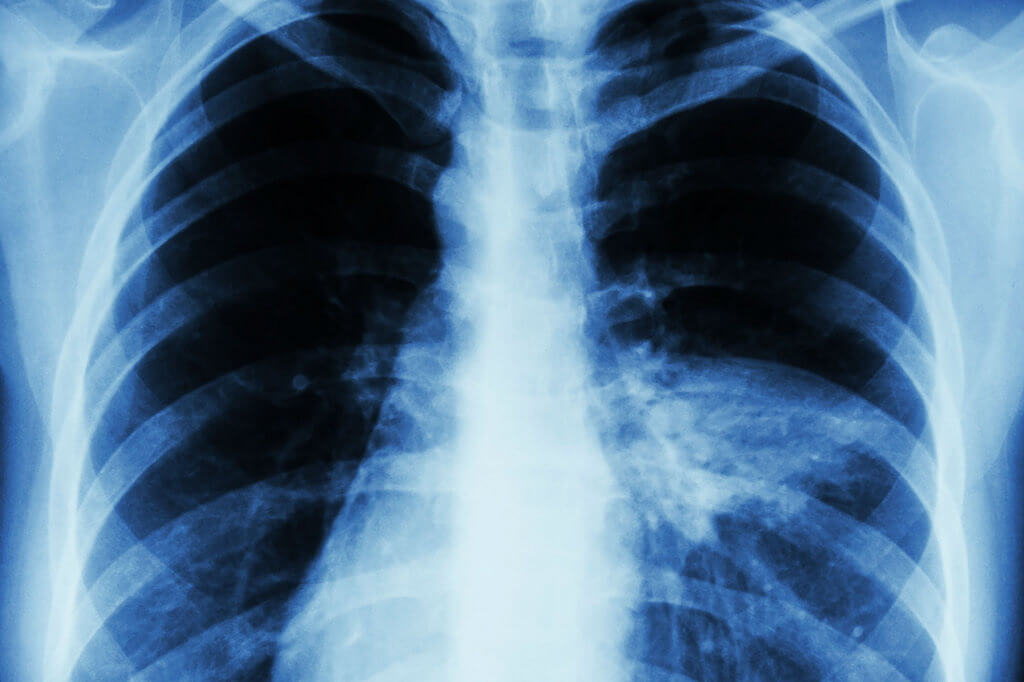

Термин “двусторонняя пневмония”, или “билатеральная пневмония”, означает, что воспаление затронуло оба легких. При этом заболевании легкие наполняются жидкостью, что снижает их способность насыщать кровь кислородом.

При двусторонней пневмонии поражены оба легких. Источник: gkbyudina.ru

Диагностика включает прежде всего рентген легких, который показывает затемнения в обоих легких, что свидетельствует о воспалении. Анализ мокроты или мазок помогает определить возбудителя инфекции. Компьютерная томография может использоваться для более точной оценки степени поражения.